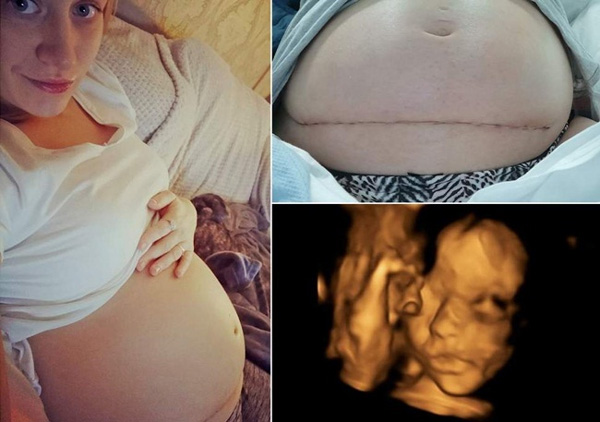

Mới đây, các bác sĩ ở Anh đã phẫu thuật thành công cho một thai nhi để chữa dị tật. Thai nhi được đưa ra khỏi tử cung người mẹ trước khi tiến hành phẫu thuật và được đưa lại vào tử cung sau khi hoàn tất quá trình này.

Việc ứng dụng công nghệ y học đã giúp các bác sĩ phát hiện dị tật nứt đốt sống lúc đứa trẻ đang ở trong bào thai sau khi người mẹ mang thai được 24 tuần. Được biết, chỉ có 4 phụ nữ ở Anh được tiến hành kỹ thuật đột phá này. Một trong số đó là thai phụ Bethan Simpson.

Theo bài đăng trên Facebook, Simpson cho hay, cô quyết định phẫu thuật sau khi phát hiện vấn đề có thể ảnh hưởng đến khả năng đi lại của con sau khi chào đời.

"Chúng tôi được đề xuất tiếp tục mang thai, chấm dứt thai kỳ hoặc lựa chọn phẫu thuật thai nhi - điều trị cho bé trước khi sinh. Chúng tôi phải chọn phương án đó", Simpson viết trên Facebook cá nhân.

Sau khi trải qua ca phẫu thuật kéo dài nhiều tiếng đồng hồ, các bác sĩ đã đưa thai nhi vào tử cung người mẹ. Thai nhi này sẽ chào đời trong thời gian tới.

"Thật buồn, khi 80% trẻ sơ sinh ở Anh bị chấm dứt thai kỳ khi cha mẹ biết đứa con trong bụng mắc dị tật này. Đó đâu phải là án tử, đứa bé có những tiềm năng như chúng ta. Rủi ro có thể xảy ra nhưng hãy suy nghĩ nhiều hơn về tật nứt đốt sống, không như trước kia nữa. Tôi cảm nhận em bé đạp trong bụng mỗi ngày, điều đó không bao giờ thay đổi. Con gái chúng tôi cho thấy, nó xứng đáng với cuộc sống này như thế nào", Simpson nói.